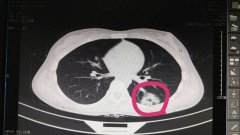

日前,我院急診科接到120通知,接回一車禍病人,入院時表述胸腹部疼痛,并呈現出血壓下降……